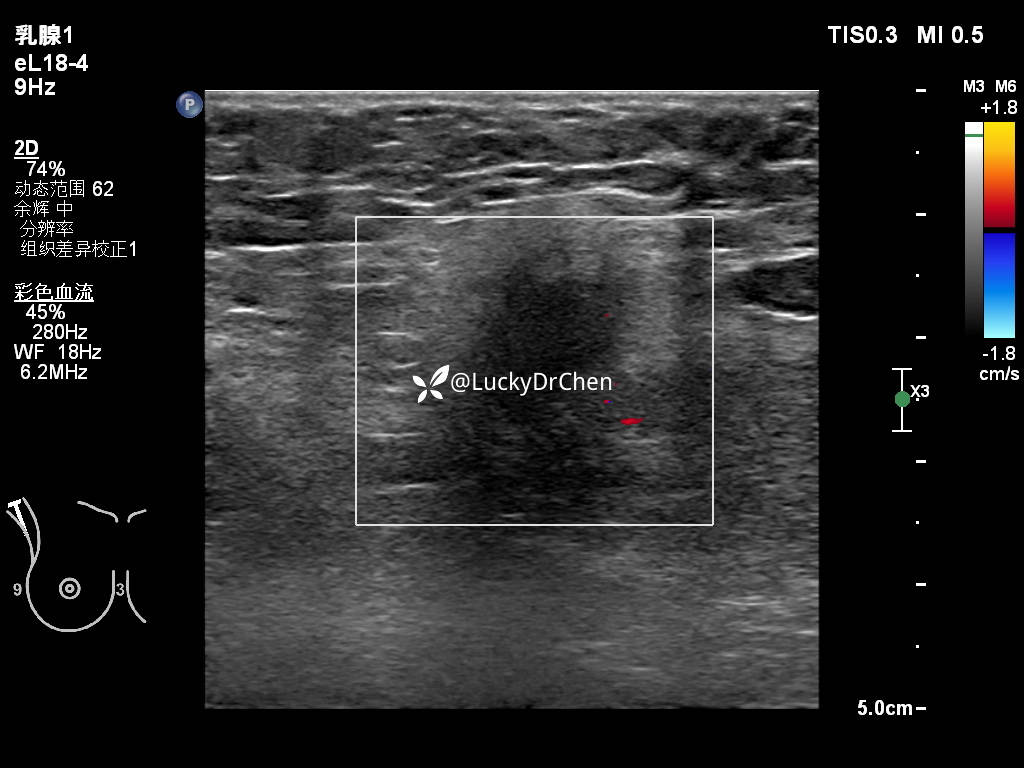

右侧腋下低回声,形态不规则,边界不清晰,周边高回声晕

可见点状血流信号